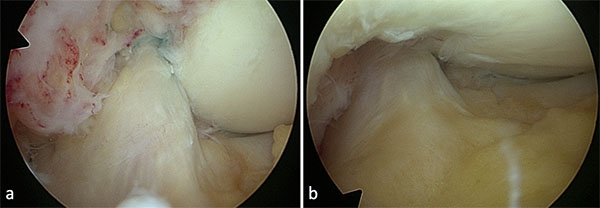

Por último, se realizan microperforaciones en la pared interna del cóndilo externo con el objetivo de estimular la médula ósea y la liberación de factores medulares que mejorarian la cicatrización del ligamento (figura 8, video 7).

Figura 8: Se realizan microperforaciones en la pared interna del condilo femoral externo para estimular la medula ósea y liberación de factores que estimulen la cicatrización.

Una visión artroscópica final confirma que la rodilla se extiende completamente y las fibras del ligamento se encuentren tensas y reducidas en el fémur (fig. 9, video 8).

Figura 9: Visión final de la reparación del LCA con la rodilla en flexión (a) y en extención (b).